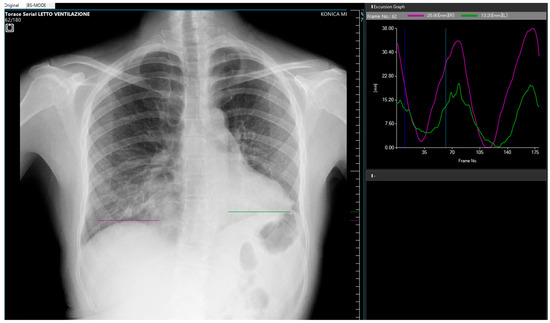

Dynamic Digital Radiography in Ehlers–Danlos Syndrome: Visualizing Diaphragm Motility Impairment and Its Influence on Clinical Management